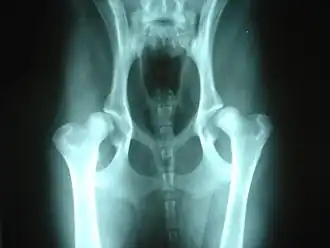

Fokmaatregelen

In een poging deze erfelijke ziekte weg te selecteren, worden röntgenfoto's gemaakt van de heupgewrichten van fokdieren voor die als fokdier ingeschreven worden in een stamboek. Een onderzoek op heupdysplasie is in het algemeen mogelijk op een leeftijd van 1 jaar.